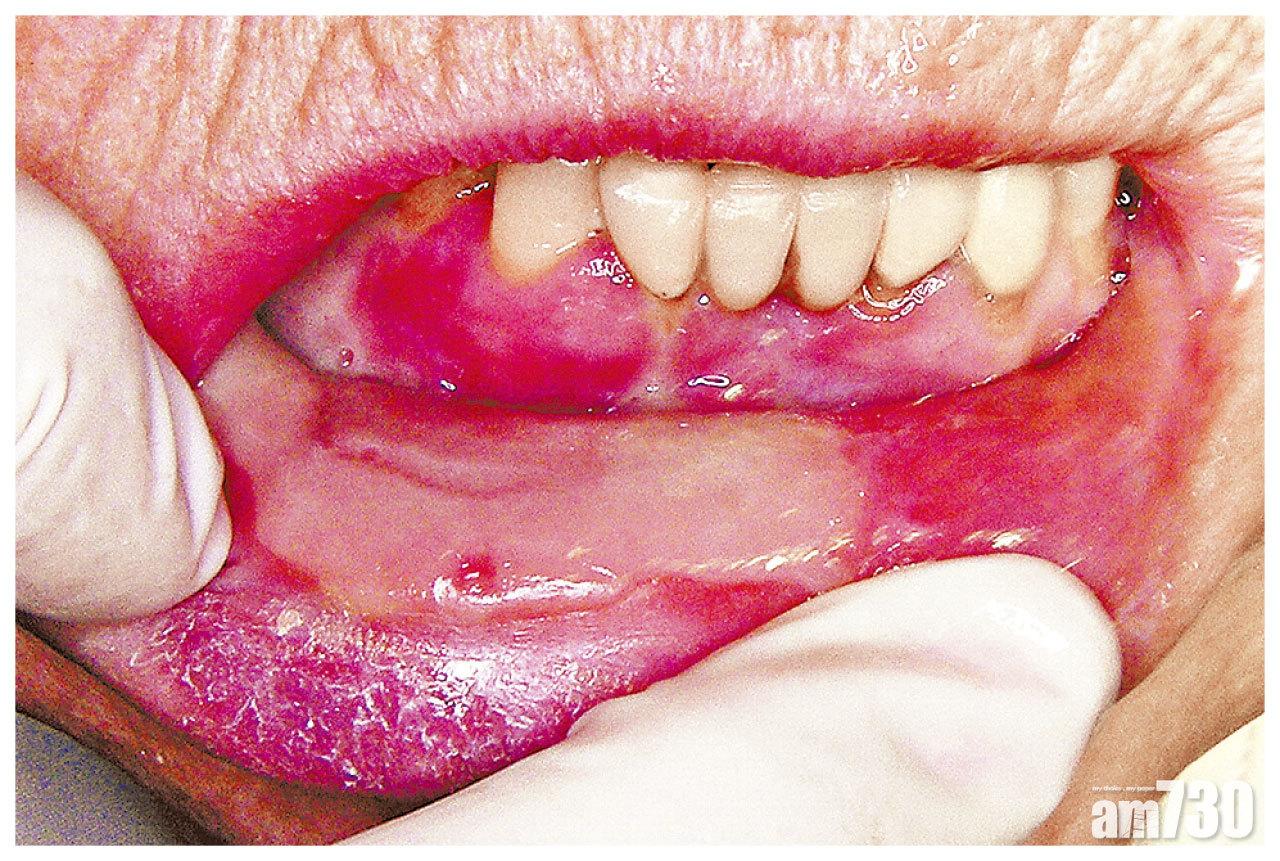

癌症患者的治療副作用因人而異,亦視乎化療所用的藥物、電療的次數和劑量而定。臨床腫瘤科專科醫生施俊健指,較常見有脫髮、噁心、免疫力下降等,「因為電療和化療除破壞癌細胞外,亦會破壞生長快速的正常細胞,所以臨床上也常見口腔黏膜炎,尤其頭頸癌患者。口腔黏膜炎多於化療後4至5天出現,7至10天形成潰瘍,而且範圍變大、數目增加;而口腔黏膜接受中度劑量或以上電療,也較易出現此副作用。」如果情況嚴重,患者或感咀嚼、吞嚥困難,甚至無法進食要經鼻管輸入營養液,亦有可能影響治療進程。

口腔黏膜炎可導致吞嚥困難,影響食慾。